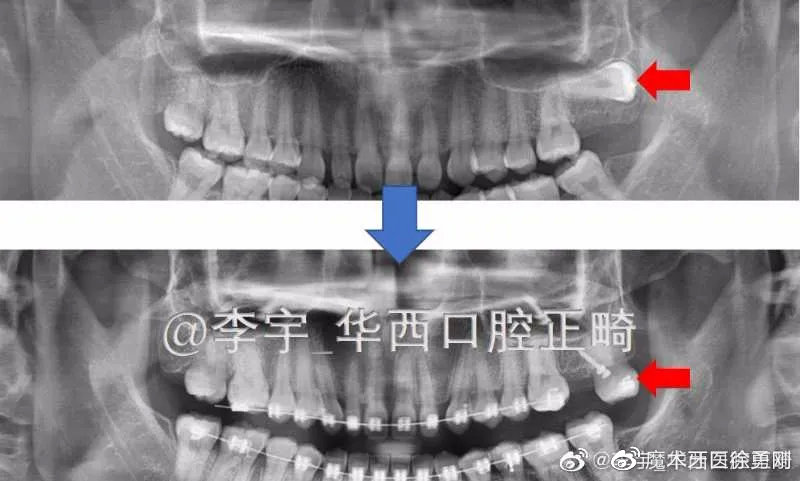

3,如果患者问题较多较重,如:非常规拔牙(因蛀牙拔了靠后的磨牙等),后牙区存在锁颌(一种严重的后牙区不良咬合),也会使治疗时间延长。

有些复杂的病例,多半都是出自正畸大师之手:

在微博上,有很多的正畸大师,经常分享一些复杂病例供同行们评价,赏心悦目。同时,也有不少正畸失败的患者在吐槽、指责Ta们的医生,而且我从微博、贴吧、百度里发现,有一些治疗失败的患者,她们追悔莫及、欲哭无泪的控诉,就跟那些深受“美容冠”伤害的人一样,明显发生了抑郁症倾向。这些失败病例的表现多种多样,有咬合错乱的,有前牙牙根暴露的,有颞颌关节紊乱的,而这些多数都缘于设计失误。